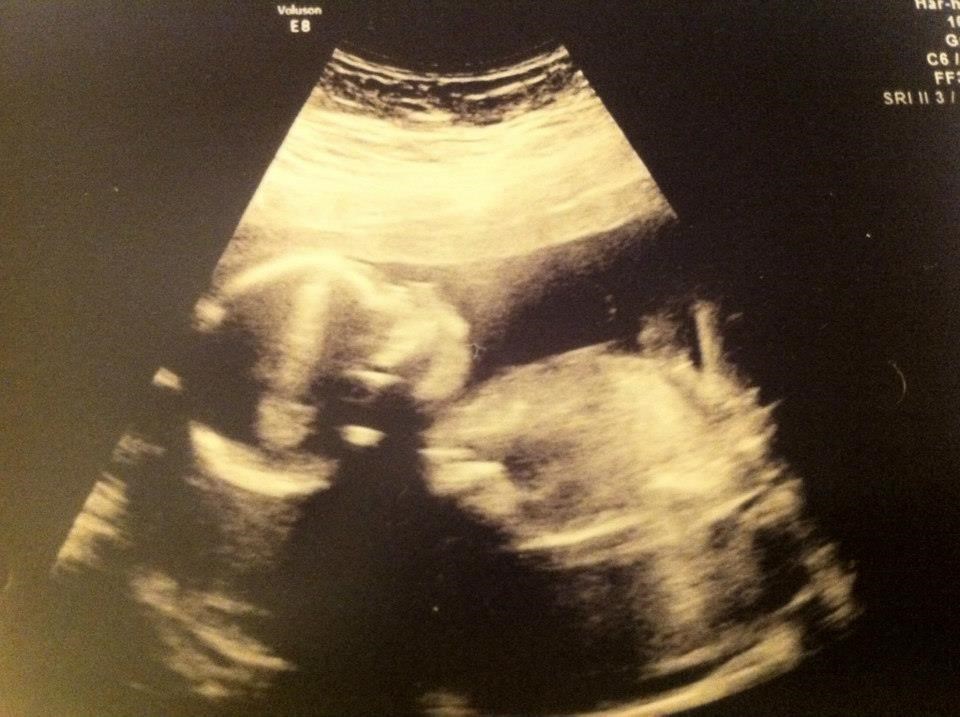

Jeg må hellere lige få skrevet en update på MD scanningen i mandags d. 11/3 .. Scanningen viste at alt så rigtigt fint ud ved bassen <3 Organerne så ud som de skulle, hjertet bankede fint og 3 kar i navlesnoren. Bassen vejede 270 gram <3

Det var det herfra og så afslutter jeg lige med et billede